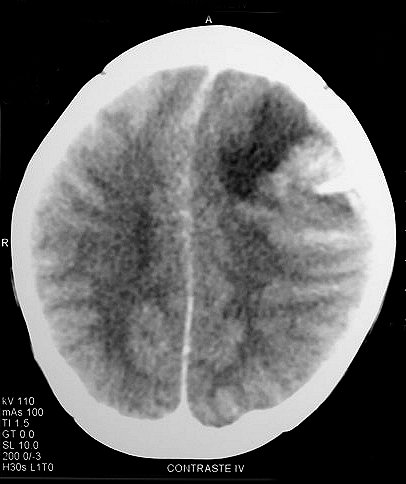

Эпендимобластома — редкая эмбриональная опухоль больших полушарий головного мозга, имеющая признаки эпендимарной дифференцировки в виде скоплений истинных розеток. В подавляющем большинстве случаев она обнаруживается у детей в возрасте до 5 лет. Прогноз при эпендимобластоме неблагопрятный. У всех больных в короткие сроки развиваются послеоперационный рецидив и имплантационные метастазы.

Выживаемость пациентов обычно не превышает одного года. Макроскопически опухоль имеет вид плотного, четко отграниченного бело-розового узла, расположенного преимущественно перивентрикулярно. Под микроскопом ткань новообразования состоит из мелких мономорфных клеток с гиперхромными ядрами. В отдельных участках выявляются скопления эпендимарных розеток.